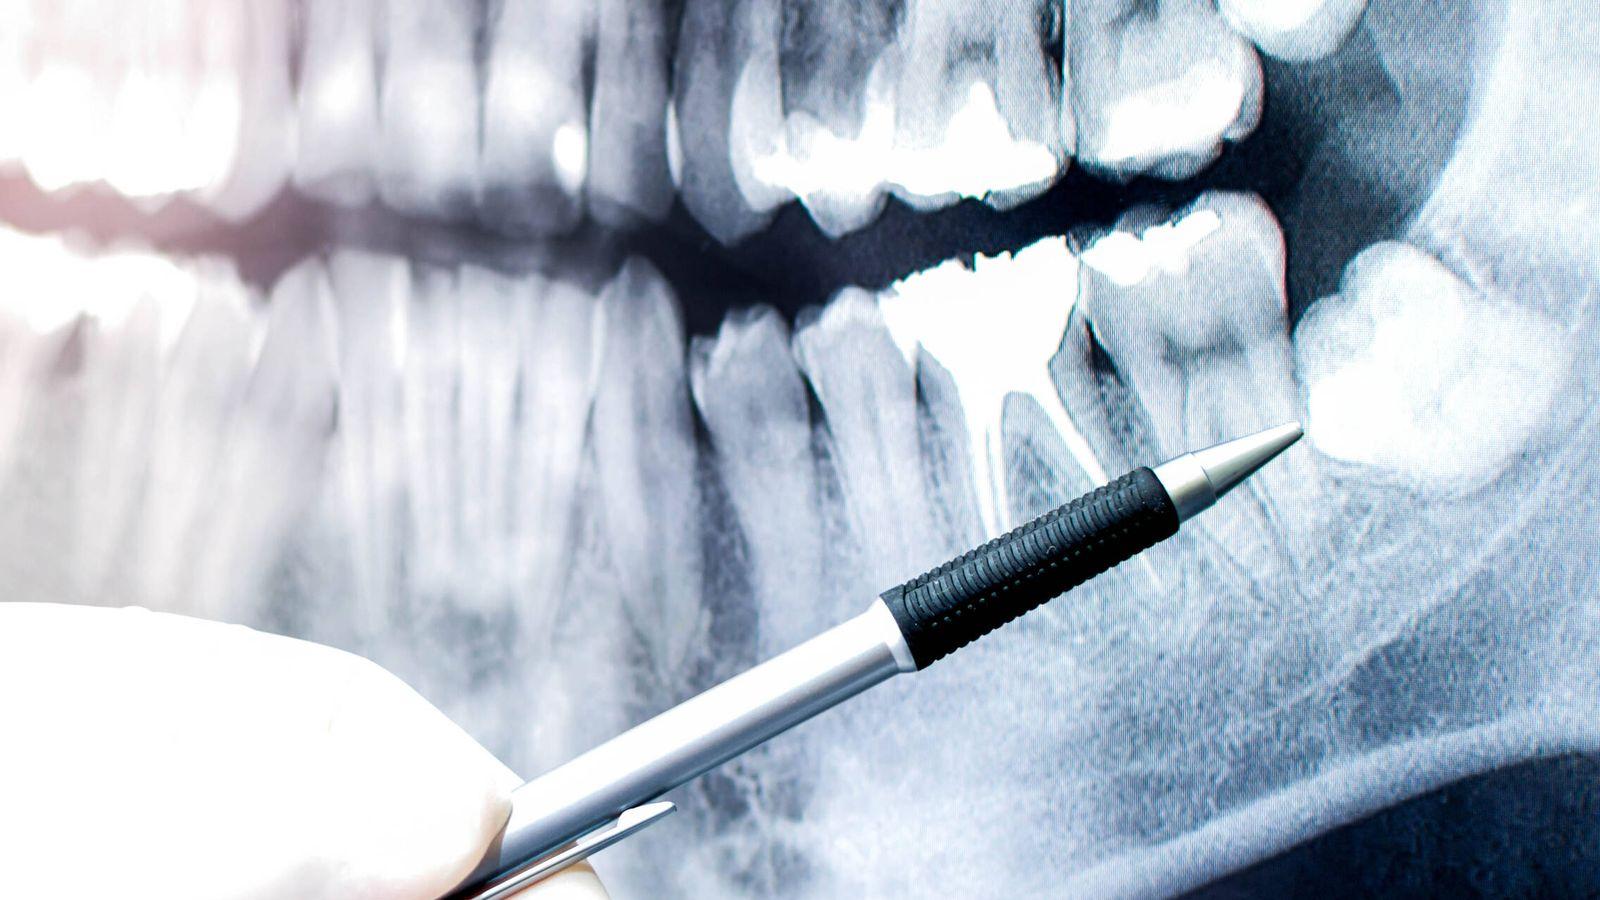

Dental Tooth Removal In Dubai Bleeding Control Guide

Dental Tooth Removal In Dubai may cause mild bleeding for a short period after the procedure, which is completely normal. Patients visiting a trusted dental clinic in Dubai are usually advised on how to manage bleeding after removal of teeth affected by severe tooth decay, gum infection, or damage. In modern dental care, bleeding is controlled effectively using simple and safe techniques.